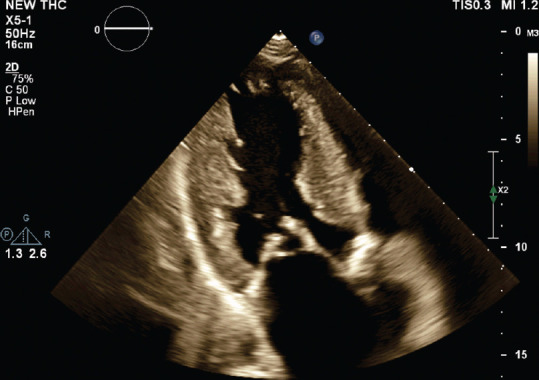

A Rare Case of Intramitral Valve Ring in the Setting of Shone Complex Diagnosed by Echocardiography.

一例通过超声心动图诊断出 Shone 复合物的罕见瓣膜内环。